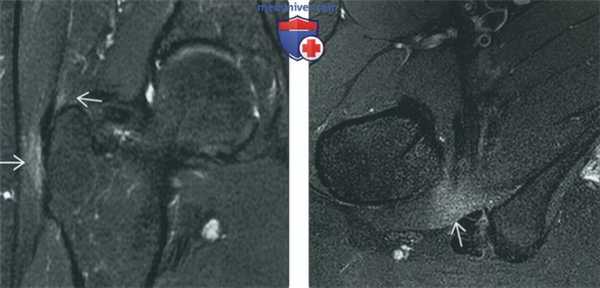

(Слева) МР-артрография в режиме PD FS, сагиттальный срез: визуализируется симптом печенья «Орео» - гиперинтенсивная жидкость между хрящом и субхондральной пластинкой кости, что соответствует отслоению хряща. Для постановки диагноза данные изменения должны выявляться как минимум на двух срезах в одной плоскости или на одном срезе, но в двух плоскостях.

(Справа) МР-артрография в режиме Т1ВИ FS, коронарный срез, этот же пациент: подтверждается отслоение суставного хряща, при этом медиальнее отмечается его глубокий дефект. Также выявляется разрыв суставной губы. (Слева) МР-артрография в режиме Т1ВИ, коронарный срез: визуализируется затек контрастного препарата между отслоенным участком суставного хряща и субхондральной пластинкой кости. Целостность хрящевого лоскута нарушена с латеральной, но не с медиальной стороны.

(Справа) МР-артрография в режиме Т1ВИ FS, сагиттальный срез: отмечается истончение суставного хряща в верхнем отделе головки бедренной костив и прилежащем отделе вертлужной впадины. Причиной истончения хряща стала травма, полученная при игре в футбол.

(Справа) МР-артрография в режиме Т1ВИ FS, коронарный срез, этот же пациент: подтверждается отслоение суставного хряща, при этом медиальнее отмечается его глубокий дефект. Также выявляется разрыв суставной губы.

(Слева) МР-артрография в режиме Т1ВИ, коронарный срез: визуализируется затек контрастного препарата между отслоенным участком суставного хряща и субхондральной пластинкой кости. Целостность хрящевого лоскута нарушена с латеральной, но не с медиальной стороны.